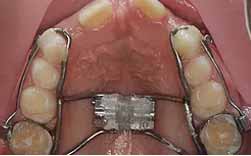

Os diastemas devidos à diminuição da largura das coroas dos incisivos laterais superiores ou a um freio fibroso, só devem ser tratados após a erupção dos 2º molares definitivos, aos 13 anos.